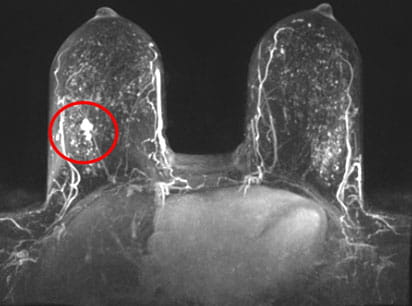

Abbreviated breast MRI scanAbbreviated breast MRI for dense breast tissue.

One-year data show that the abbreviated breast MRI program at UH has identified 19.9 breast cancers per thousand studies, Dr. Marshall says.

“That’s really, really good,” she says. For comparison, a prospective, multi-institutional study published last February in JAMA showed that abbreviated breast MRI detected 11.8 cancers per thousand studies.